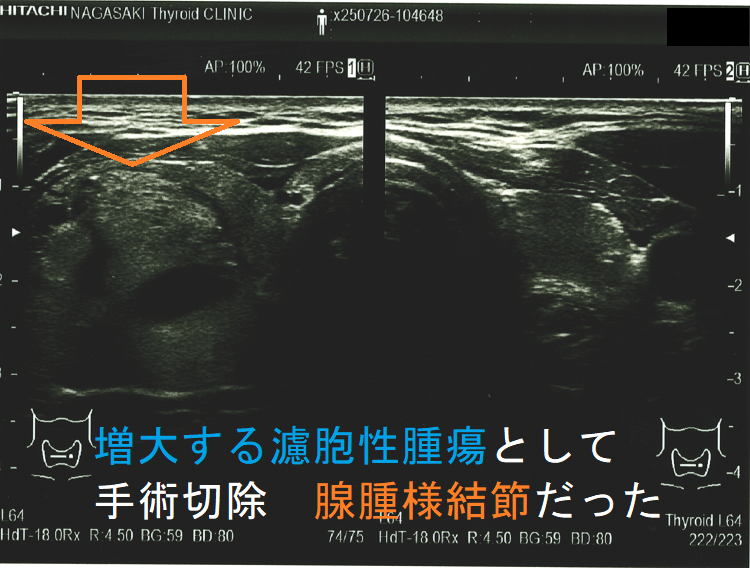

ある意味、腫瘍の増大速度程、悪性の可能性を疑わせる所見は他にありません。急激な速度で大きくなる濾胞性腫瘍は、異常な速度で細胞増殖がおこっています。それは高い確率で甲状腺濾胞癌であると考えざる得ません。(サイズ増大で甲状腺濾胞癌と診断)

- 腺腫様甲状腺腫:14 例(10%);やはり、エコー・細胞診での鑑別が難しいものがありますので

超音波(エコー)画像上、腺腫様結節と甲状腺濾胞性腫瘍は類似しますが

- 被膜があれば甲状腺濾胞性腫瘍ですが、被膜がなければ腺腫様結節[ただし腺腫様結節でも、腫瘍の境界部のハロー(halo:低エコー帯)は、不完全な形で存在します]

- ハローが全周性に認められれば、甲状腺濾胞性腫瘍の可能性が高い。(ただし、ハローの一部途絶、 肥厚等は甲状腺濾胞癌の可能性を考えます。)

- 中心に達する栄養血管がなければ腺腫様結節ですが、あれば甲状腺濾胞性腫瘍・腺腫様結節いずれの可能性もあります。